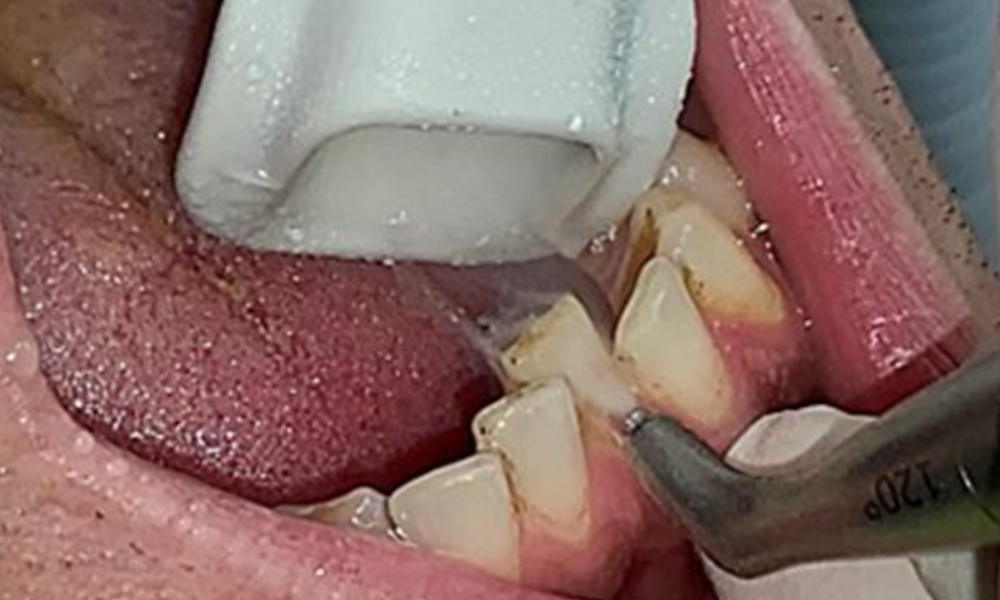

Целта е да се контролира рискът от заболяване чрез отстраняване на супрагингивалния и субгингивалния биофилм. Инструментите трябва да бъдат подбрани въз основа на нуждите на пациента. Първо трябва да се отстранят зъбният камък и всички конкременти с помощта на ултразвукови и/или ръчни инструменти (фиг. 10).

Почистването на междузъбните пространства с подходящи четки или конци за премахване на биофилм по време на посещението при зъболекар е задължително (фиг. 14).